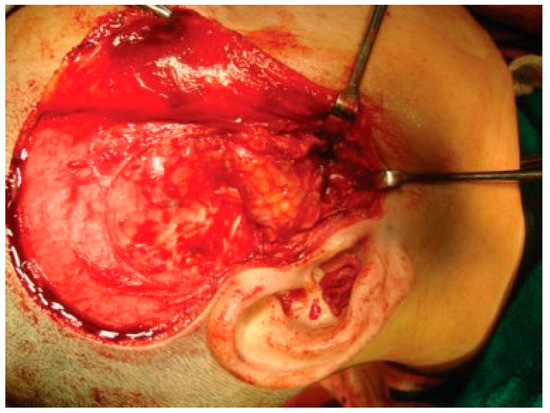

Figure 5. Intraoperative passive mouth opening.

Reconstruction of the TMJ after release of ankylosis assumes paramount importance in terms of restoration of facial form and function. The goals of treatment in all the patients were the release of ankylotic mass, restoration of normal jaw form and function, symmetric growth of the mandible in children, and most importantly the prevention of reankylosis. All interpositional arthroplasties are to some extent the autogenous reconstruction of the morbid ankylotic TMJ after resection of the ankylotic mass. Merriam Webster Dictionary defines reconstruction as the act or process of building something that was damaged or destroyed again. Reconstructive surgery refers to a procedure whose goal is intended to restore form and function in structures deformed or damaged by disease, congenital anomaly, tumor, trauma, or infection (Farlex Partner Medical Dictionary Farlex 2012). The treatment of TMJ ankylosis is individualized based on the severity of ankylosis, age of the patient, and other patient factors. We have outlined our experience following Kaban’s protocol in the management of TMJ ankylosis. It is of paramount importance to obtain passive and maximal mouth opening using this protocol in terms of adequate resection and ipsilateral or contralateral coronoidectomy whenever required followed by aggressive physiotherapy (Figure 5 and Figure 6). Physiotherapy was started on third day postoperatively using Heister mouth gag five times a day during the hospital stay of the patient. This device was purchased by the patient after discharge from the hospital for physiotherapy at home. The MIMO and excursive movements were recorded at various follow-ups for all the patients. No intermaxillary fixation/elastics were applied to any of the patients in the series.